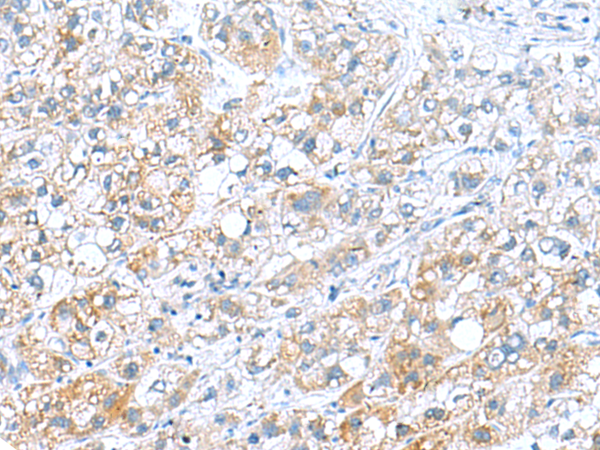

IHC positive control: |

Human liver cancer |

IHC Recommend dilution: |

50-200 |